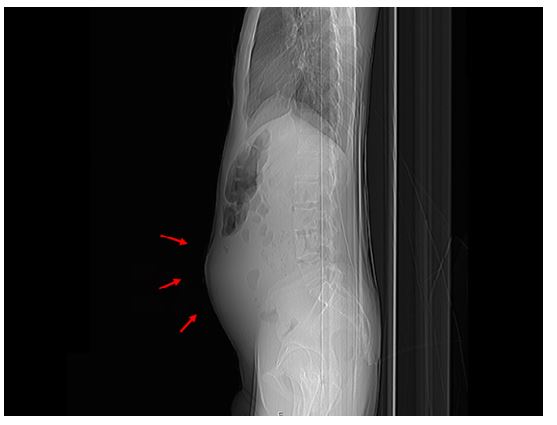

Physical examination revealed a thin appearance (body mass index = 16.9 kg/m2, z-score = -1.33), a distended and painful abdomen with tenderness, and a palpable mass with a rock-hard consistency in the hypogastric region. Abdominal radiograph (Figure 1) showed marked abdominal distension without air-fluid levels. Abdominal ultrasound revealed a large heterogeneous retroperitoneal mass in the midline of the abdomen and another lobulated hypoechoic mass near the rectum, suggestive of conglomerate lymph nodes or neoplasm.